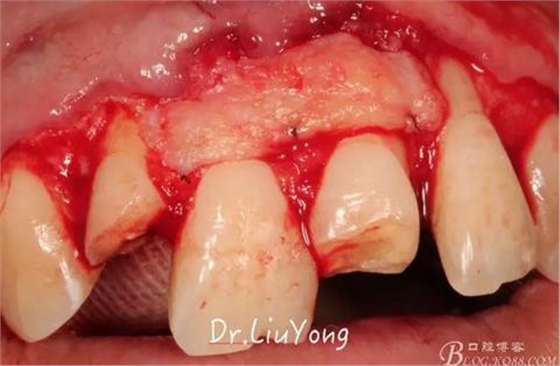

A區(qū)腭側(cè)所移取的上皮下結(jié)締組織瓣,如上圖